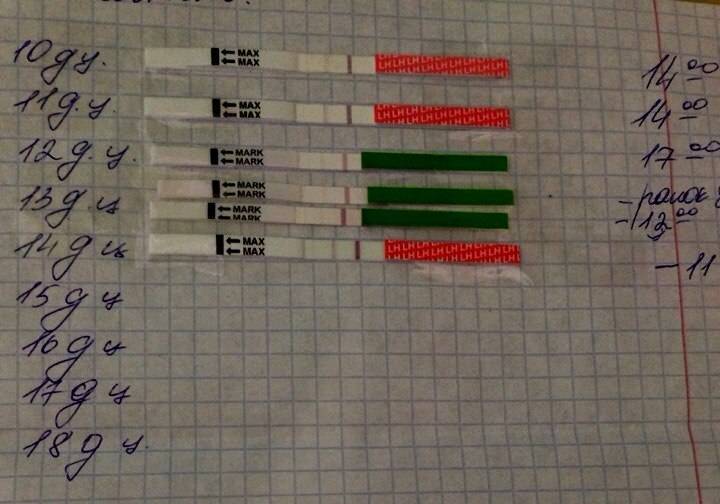

Рекомендации по зачатии